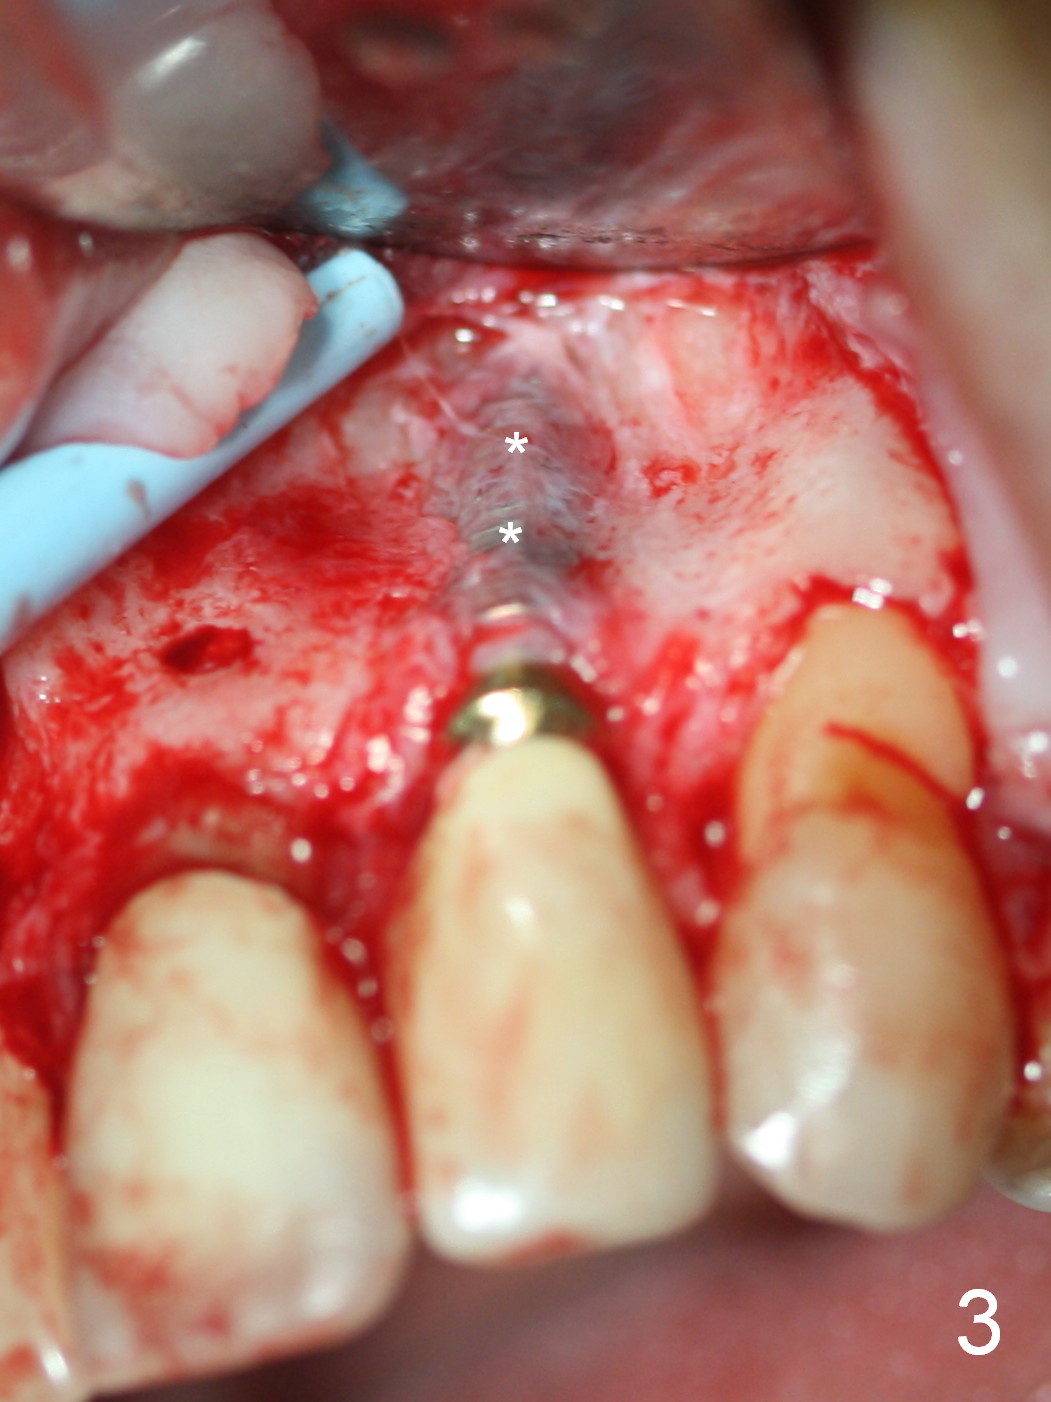

The 57-year-old lady does not like the crown at the site of #10 immediately when it is cemented (Fig.1). When the upper lip is retracted, it appears that the implant is immediately underneath the gingiva (Fig.2 *). It is slightly tender when palpated. The patient refuses CBCT. When the buccal flap is raised, the implant is found to be exposed buccally (Fig.3). When it is removed, the coronal portion of the palatal wall is thin (Fig.4). It appears that there is bone in the mid and apical thirds of the palatal wall, where an osteotomy is initiated using a 1.2 mm pilot drill. When the latter reaches 18 mm from the crest, the nasal floor appears to be perforated. The latter is confirmed by PA (Fig.5). As the osteotomy are increasing in diameter, force is applied as palatally as possible without perforating the palatal wall too much. When a 3.5x20 mm implant is placed (30 Ncm), it is palatal to the labial wall. The defect is filled by allograft and Osteogen, covered by long termed resorption membrane. The buccal flap is sutured (Fig.7). A proposal to place gingival graft is rejected. The implant is shown to have been positioned more or less normally (Fig.8). A removable temporary appliance is fabricated. Periodontal dressing is applied.